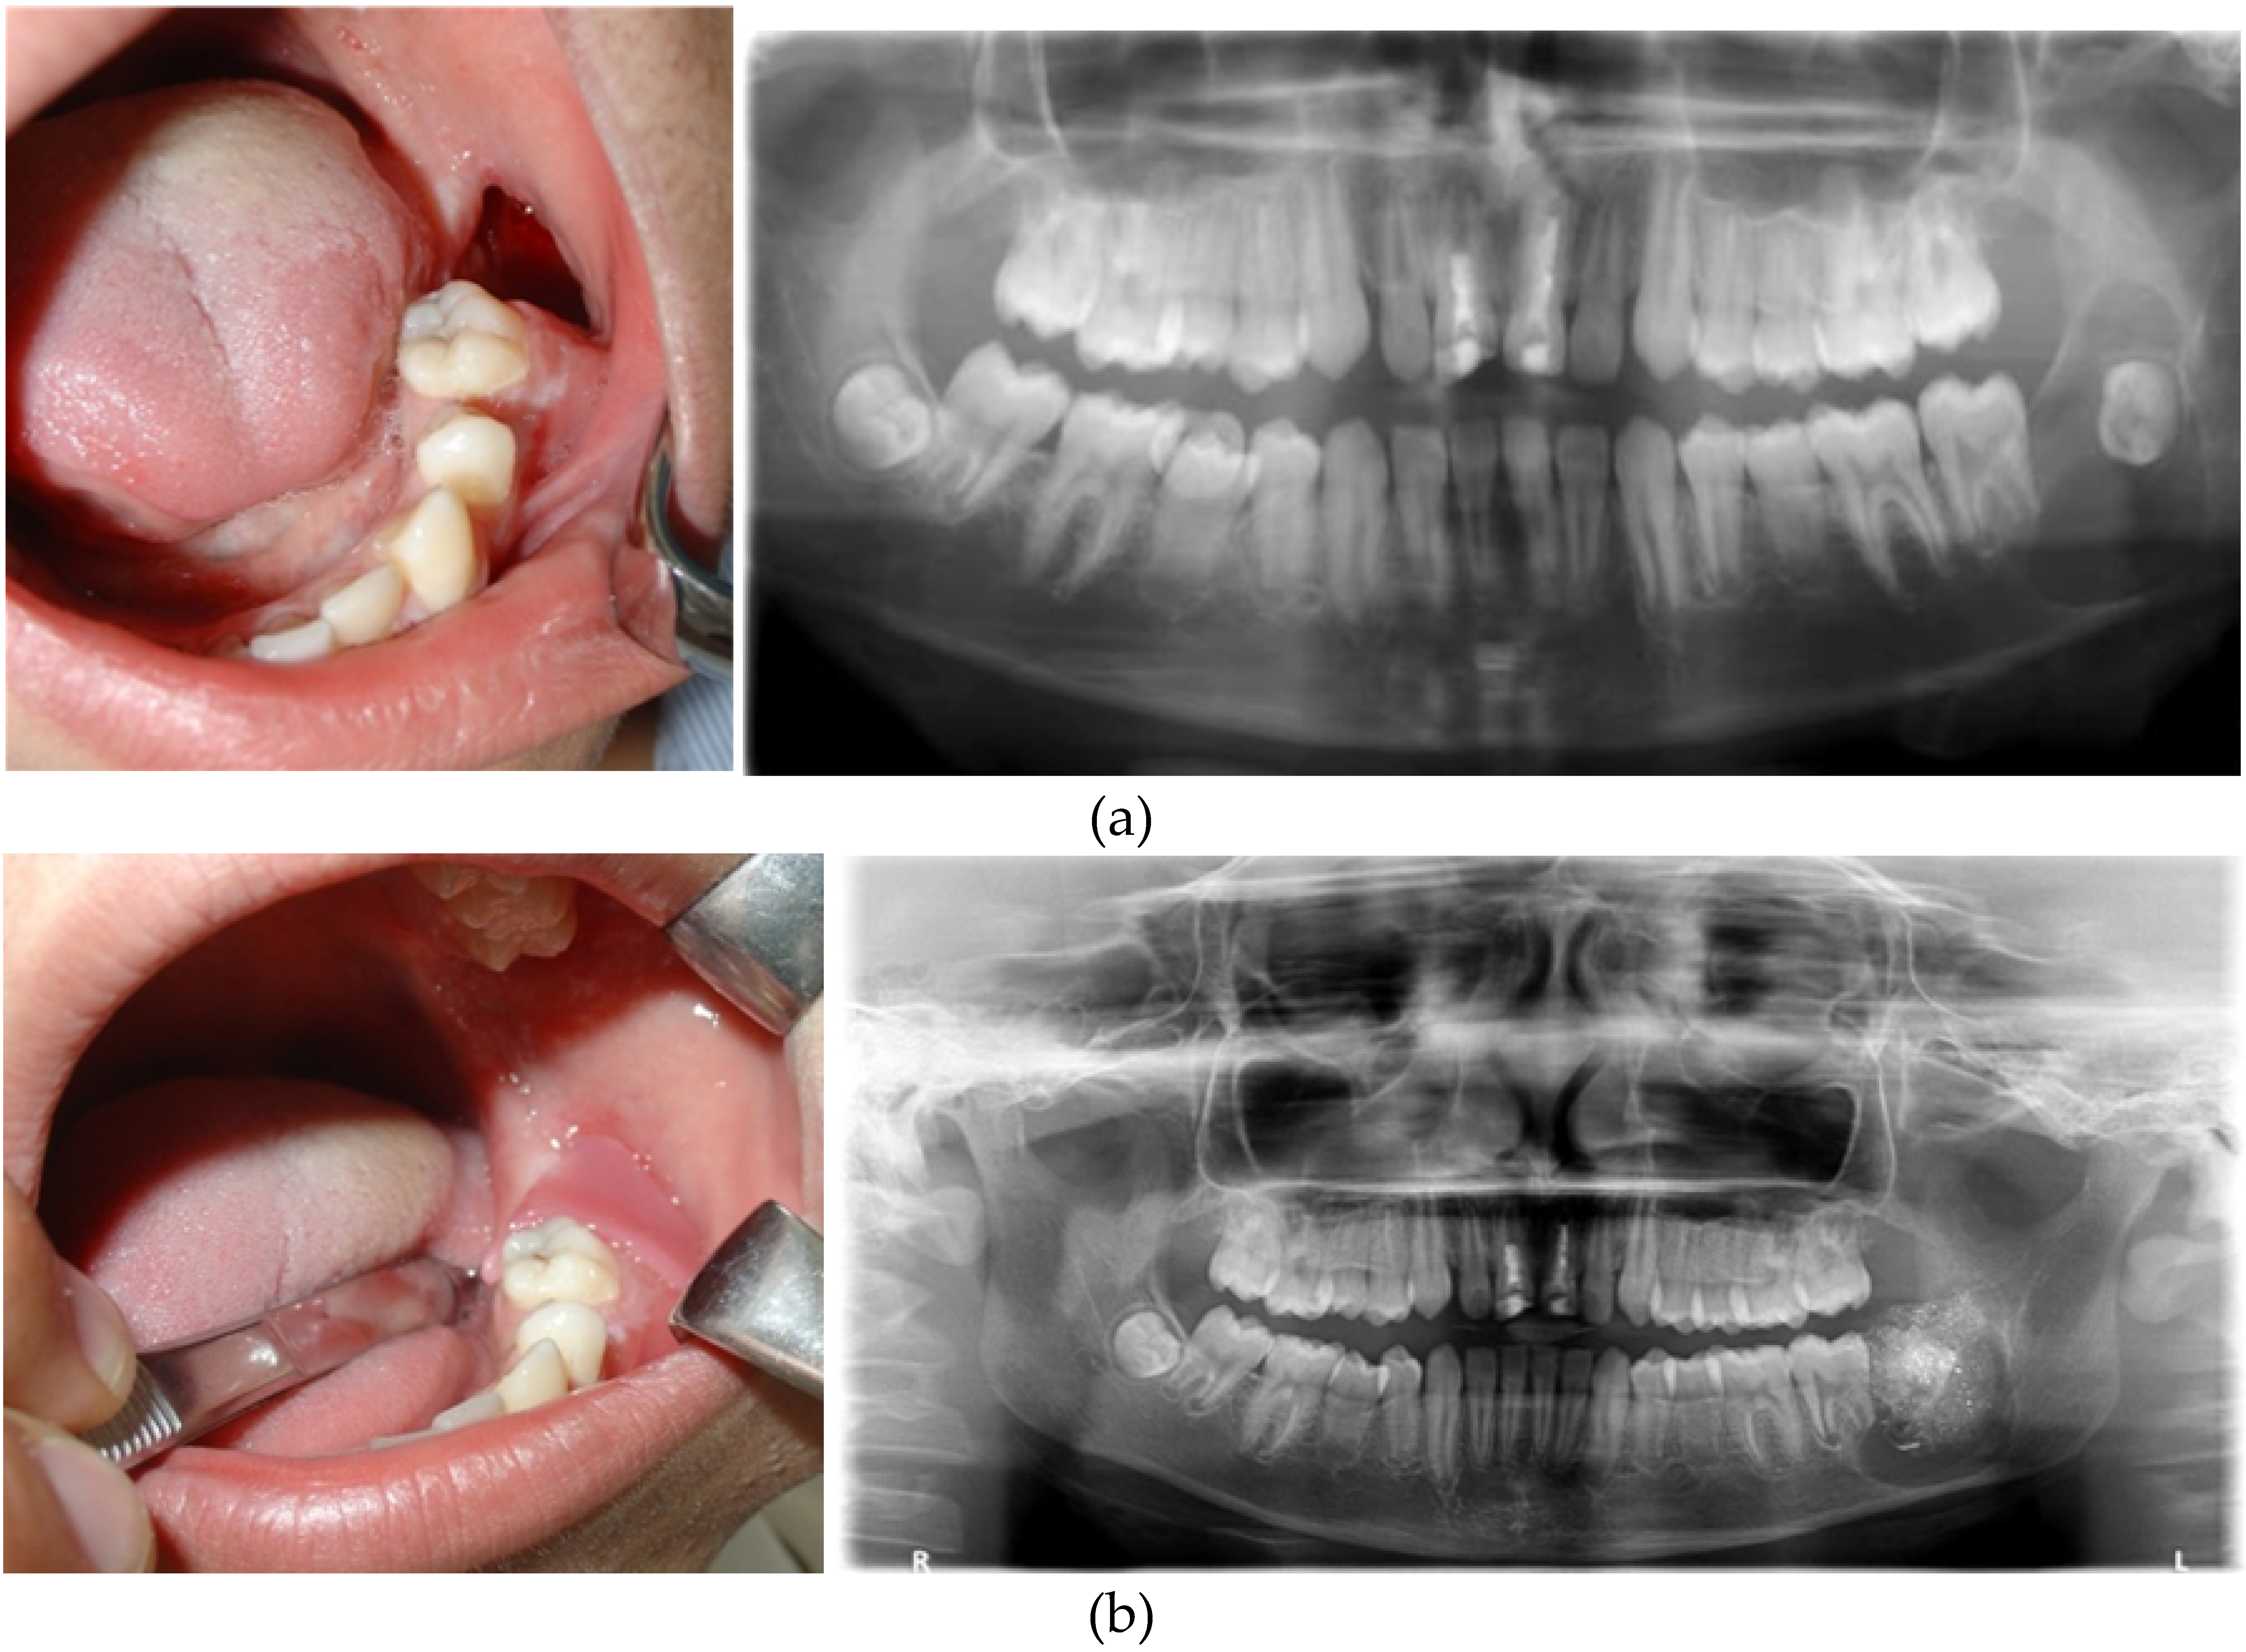

• Accurate diagnosis through imaging techniques such as X-rays, CT scans, and MRIs.

• Biopsy may be required to confirm the nature of the lesion.

• Enucleation: Removal of the entire lesion, often used for cysts.